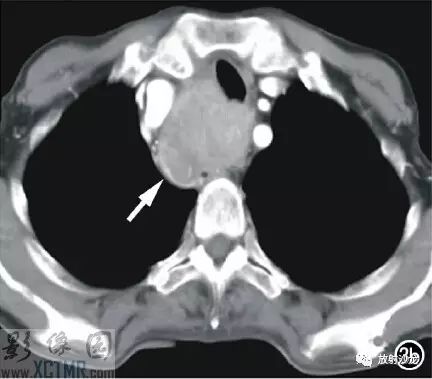

上消化道鋇餐:食管胸上段可見不規則充盈缺損,約5.6cm*4.2cm,黏膜結構紊亂,管壁不規整,對比劑通過稍緩慢,會厭動度不協調,考慮食管癌(圖2)。CT:食管胸上段見軟組織腫塊,上自杓會厭披裂,下至主動脈弓水平,腫塊邊緣清晰,密度均勻,增強掃描輕到中度不均勻強化,食管腔狹窄,氣管、右側甲狀腺、鄰近血管受壓移位(圖3),縱隔未見腫大淋巴結,診斷:食管癌可能。